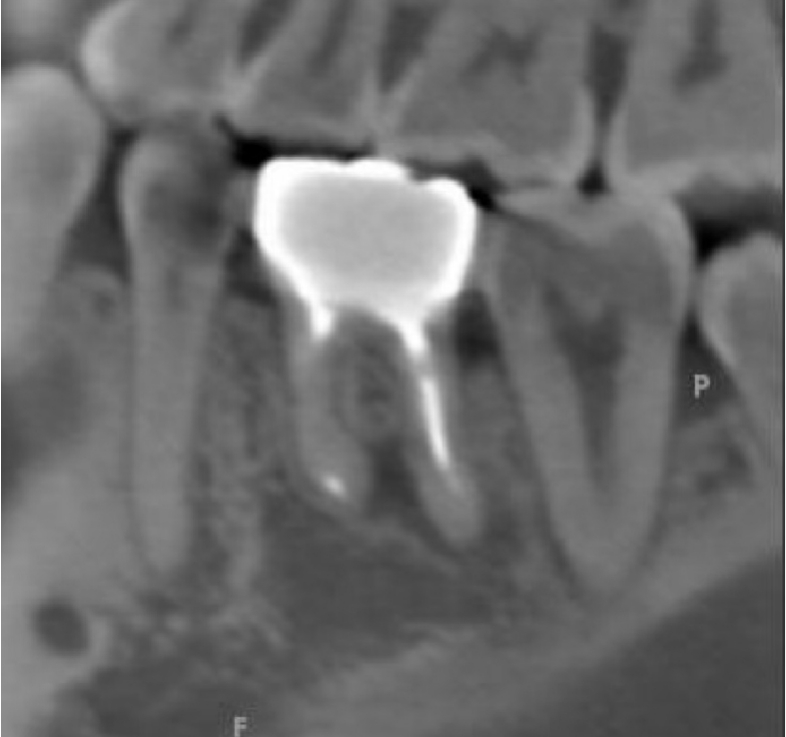

根管治療の症例

術前

術後9ヶ月

歯ぐきの腫れと膿の出口(サイナストラクト)があり、検査により原因歯を特定しました。再根管治療で根管内の感染コントロールを試みましたが症状が改善せず、CTで病変範囲を精査。

近心根切断面

遠心根切断面

上記の写真は、歯根端切除後の切断面を顕微鏡を用いて精査している写真です。 歯内療法の専門医が外科的歯内療法(歯根端切除)を行い、術後の経過で骨の回復が確認でき、良好な治癒につながりました。

年齢性別 30代・男性

主訴 右下の銀歯のところが腫れている/膿が出る(サイナストラクト)

治療部位 右下6番

治療内容 瘻孔トレースで原因歯特定 → 再根管治療 → 改善乏しく外科的歯内療法(歯根端切除・逆根管充填)

治療回数 1回(根管治療含めると3回)

リスク副作用 外科処置後に腫れ・痛み・出血が生じることがあります。状態によっては治癒が得られず、追加治療や抜歯が必要になる場合があります。

再根管治療だけでは改善が難しいケースでも、外科的歯内療法という選択肢で歯を残せる場合があります。外科を含めた難易度の高い処置まで一貫して対応できるのは、歯内療法を専門に診ている強みの一つです。「抜歯しかない」と言われた歯でも、状態次第では保存の可能性があります。